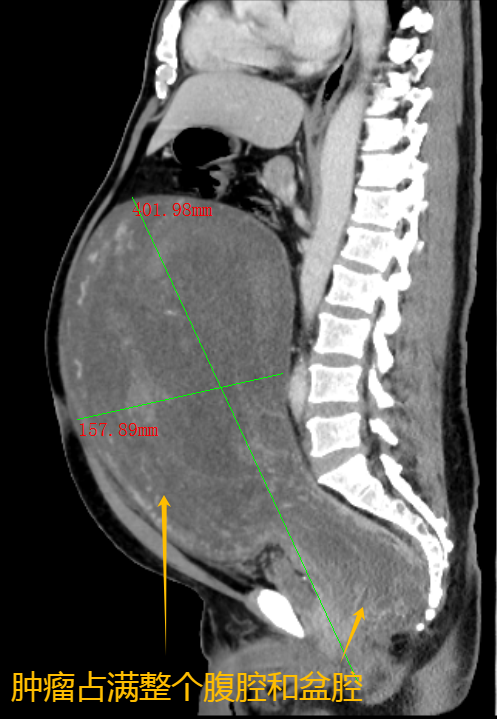

肿瘤占满男子整个盆腔和腹腔。

今年10月,在朋友的建议下,阿华来到广西中医药大学附属瑞康医院就诊。“患者的情况很危急。”该院泌尿外科一区主任、主任医师梁泰生介绍,由于患者的盆腔肿瘤已经长到了腹腔,压迫到肾脏、胃肠等器官,生命已亮起“红灯”,随时可能因脏器衰竭、呼吸道受压窒息等严重并发症而危及生命。